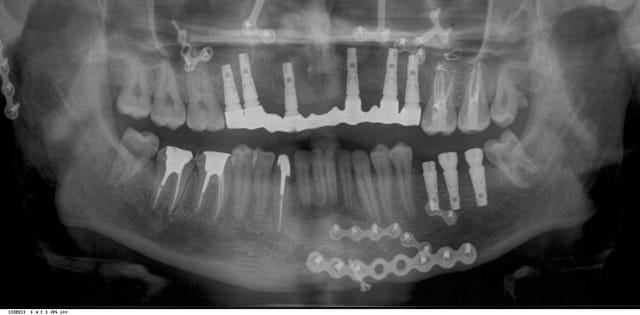

voilà, pas mal de retard sur le programme....

pano intermédiaire.

je commence les prothèses définitives dans 15 jours...

elles sont jolies tes endos mon alhoun!!! ;-)

joli MV2 sur la 26!!! et bien visible en plus, même sur la pano!

Dis, va pas falloir trop trainer pour soigner la 38...

Juste une question concernant l'armature du bridge sur implants. On dirait qu'elle n'est pas enfoncée à fond en regard de 14-15. Image radio sans conséquence ou réalité? Possibilité de bascule?

oui tonio, il y a en effet une bascule légère, mais c'est un bridge provisoire qui n'était pas sensé être porté si longtemps.

d'ailleurs, on peut remarquer une image douteuse sur M47, due à sa disparition dans la nature. je reprendrai ce traitement ( en HN), avant la pose des couronnes.

pour 26 et 27. de la même façon, le patient a disparu un certain temps, il avait un os en forte activité, et je crois que cela a accéléré l'egression de 26 et 27, qui est assez importante.

je voulais les ingrésser orthodontiquement , grâce aux conseils de dancha, mais le patient a voulu aller au plus vite.

dans 15 jours, on attaque les prothèses définitives.